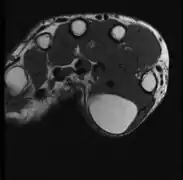

A physical exam is typically the easiest way to diagnose it. Rarely, a tissue biopsy or imaging may be required. The imaging modality of choice is magnetic resonance imaging (MRI) because it has superior sensitivity of distinguishing it from liposarcoma as well as mapping the surrounding anatomy.[22]

-

X-ray of a lipoma -

Medical ultrasonography of a lipoma in the thenar eminence: It is hyperechoic compared to adjacent muscle, and relatively well-defined, with miniature hyperechoic lines.[23] -

MRI showing lipoma of the arm -